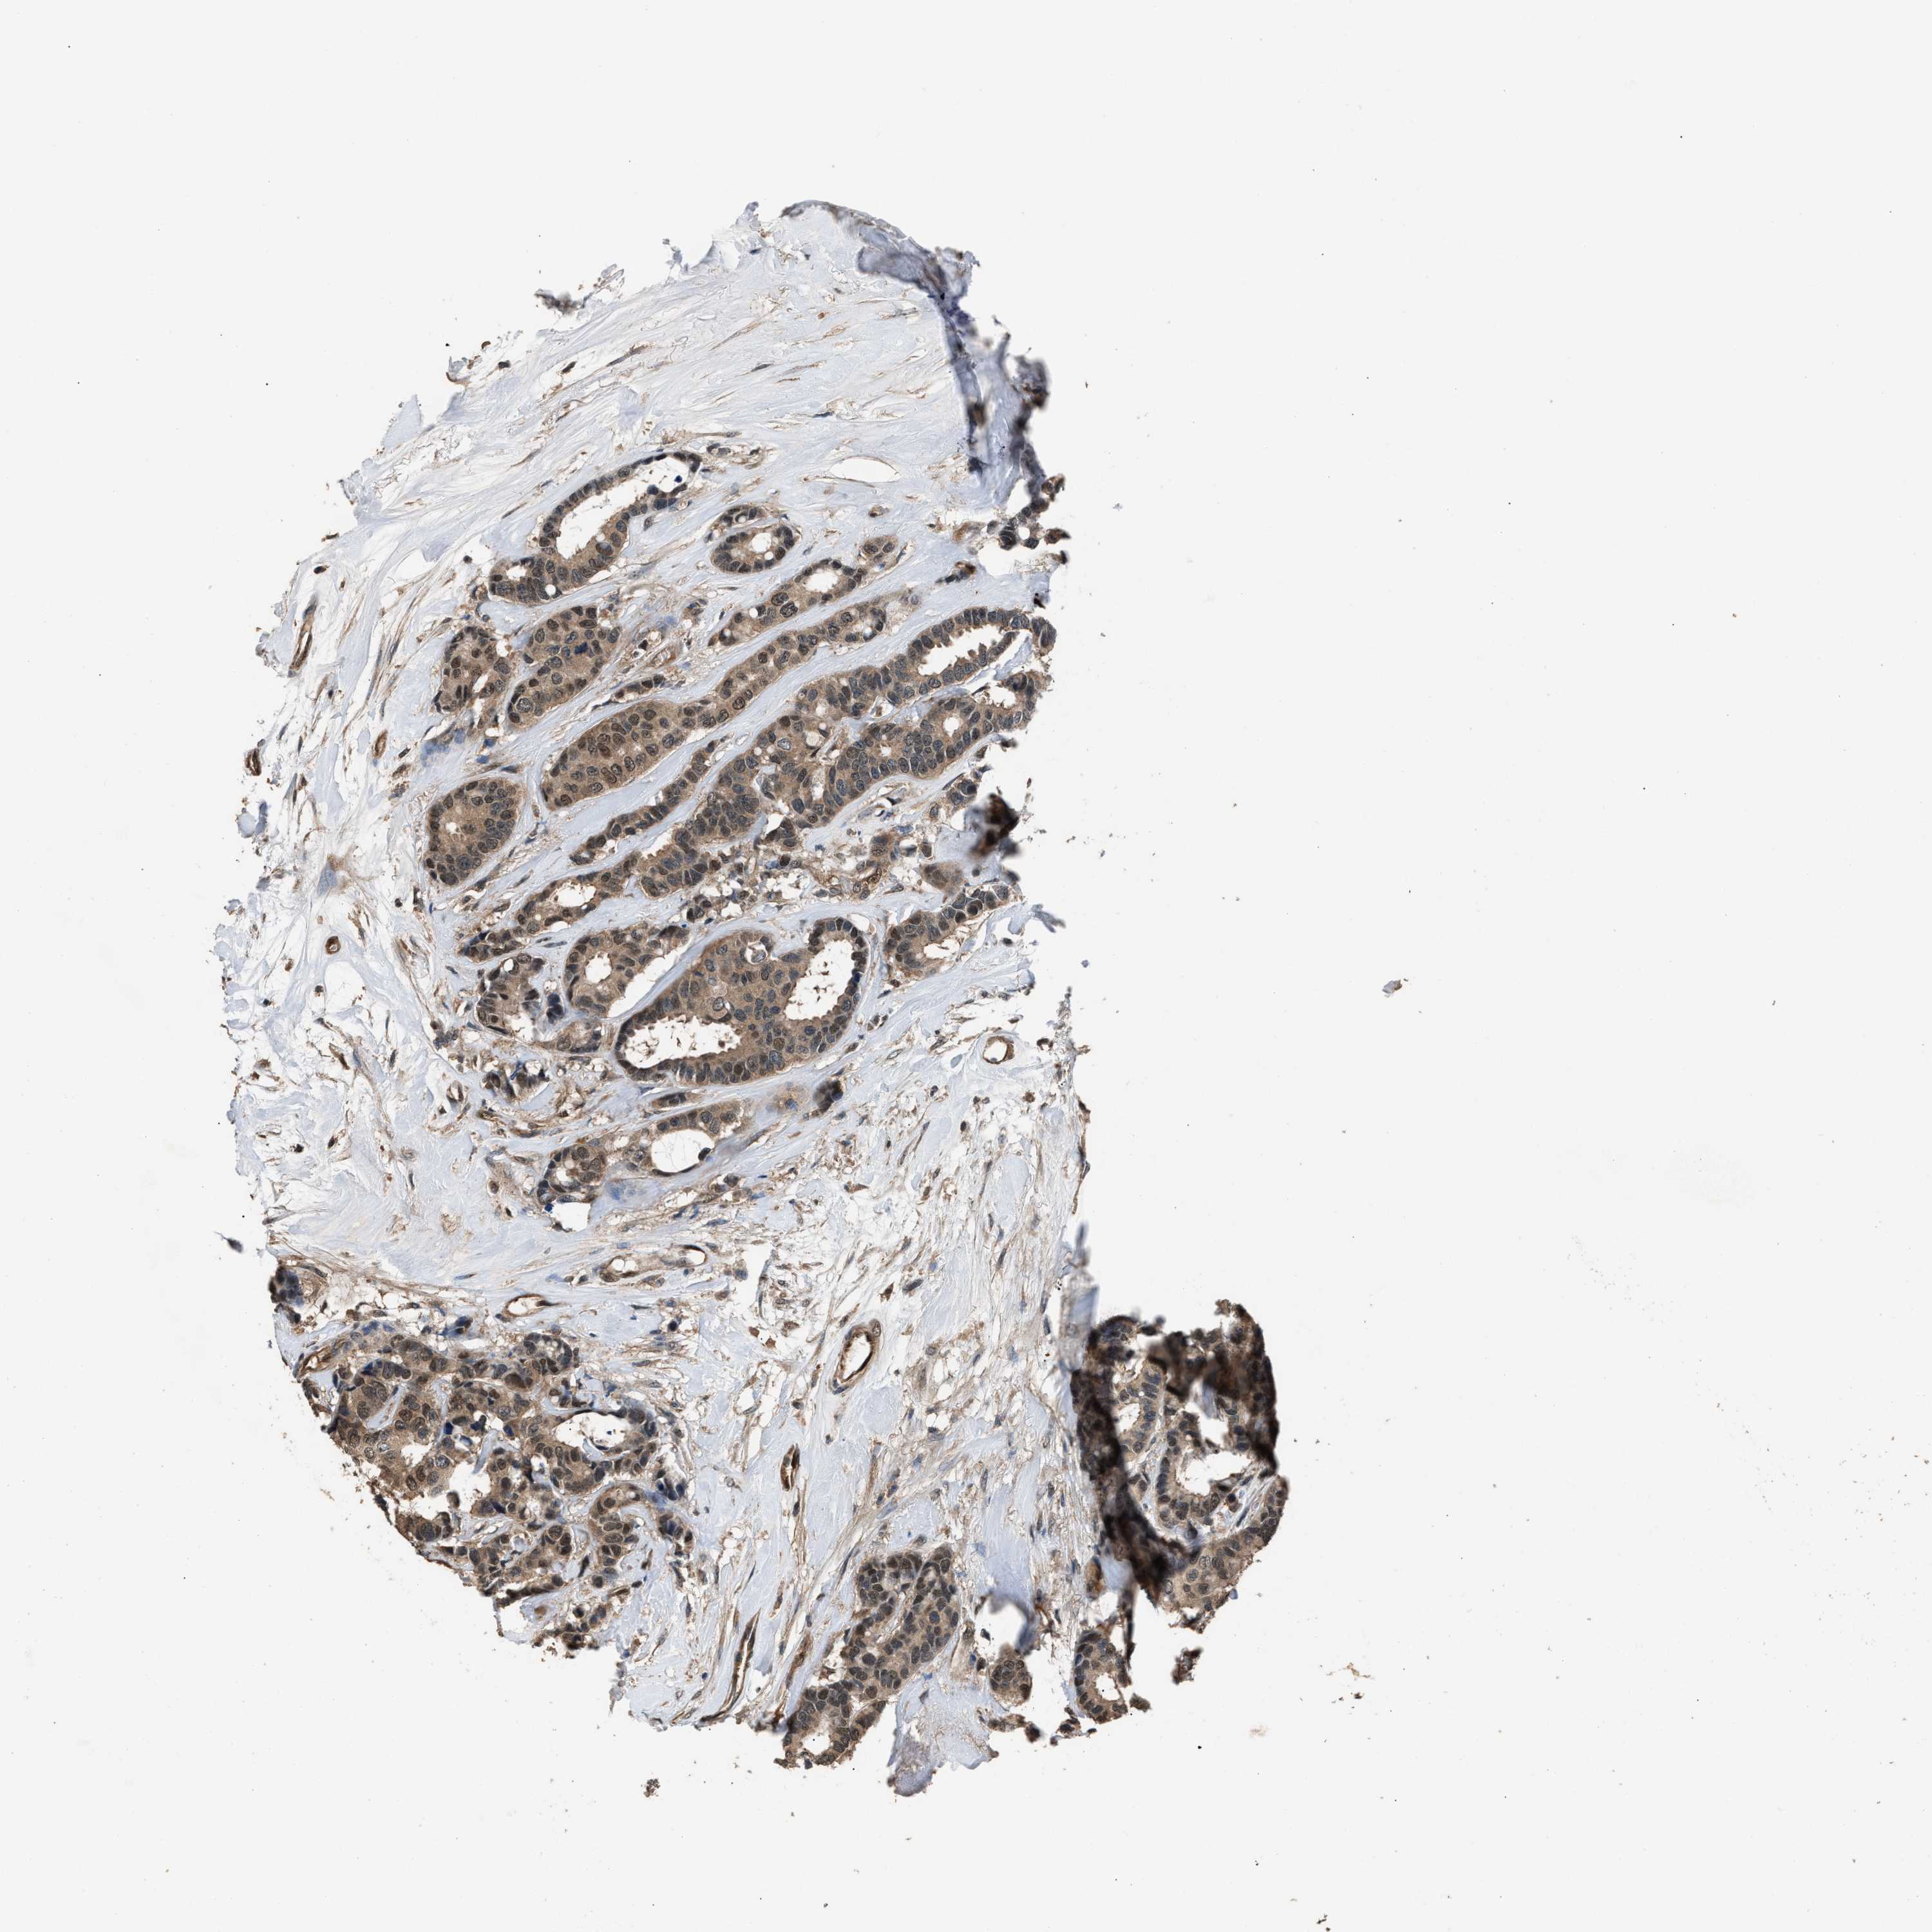

CANCER BREAST CANCER Show tissue menu

BRCA TCGA BRCA VALIDATION PROTEIN EXPRESSION

ANTIBODIES

AND

VALIDATION